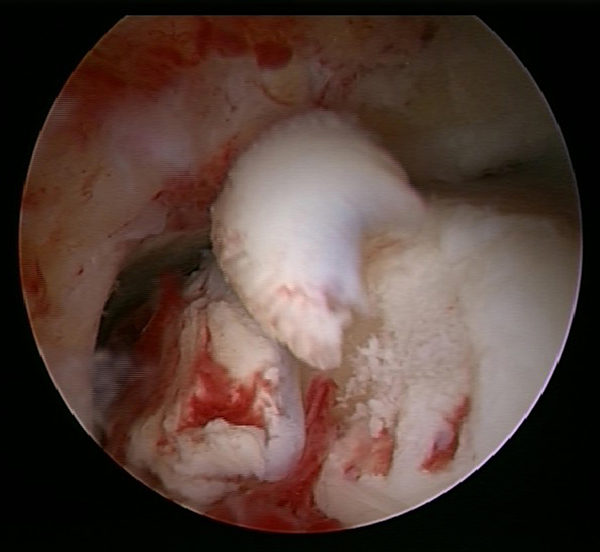

Ein aktuelles systematisches Review zur arthroskopisch-assistierten Frakturversorgung (AORIF) am Sprunggelenk identifizierte bei 495 von 782 Patienten (63,3%) chondrale Verletzungen 54. Weder durch die klinische Untersuchung noch mit konventionellen Röntgenaufnahmen oder mittels CT-Bildgebung lassen sich diese Verletzungen zuverlässig diagnostizieren. Aus diesem Grund rückt die arthroskopisch-assistierte Frakturversorgung am oberen Sprunggelenk zunehmend in den Fokus. Die Arthroskopie ermöglicht im Rahmen der Frakturversorgung sowohl die Kontrolle der Reposition als auch die Beurteilung und Therapie von intraartikulären Pathologien. Während sich die arthroskopisch-unterstützte Versorgung einiger Frakturen bereits etabliert hat (z.B. proximale Tibiafraktur) gehört der Einsatz der Arthroskopie bei der Frakturversorgung des oberen Sprunggelenks in den allermeisten Kliniken noch nicht zum Versorgungsalltag 155 Im Gegenteil, in einer aktuellen amerikanischen Datenbankanalyse des United Healthcare Orthopedic Datasets wurden zwischen 2007 und 2011 insgesamt 32 307 Patienten identifiziert, die mittels ORIF an einer Sprunggelenksfraktur versorgt wurden. In weniger als einem Prozent erfolgte eine arthroskopisch-assistierte Versorgung 55. Dem gegenüber stehen arthroskopische Studien der vergangenen Jahre, die zeigen konnten, wie häufig es zu intraartikulären Verletzungen bei Sprunggelenksfrakturen kommt. Das Risiko für diese intraartikulären Begleitverletzungen nimmt mit der Komplexität der Fraktur zu 5657. Es liegt also nahe, dass bei komplexeren Frakturen die Durchführung einer Arthroskopie im Rahmen der Frakturversorgung einen positiven Effekt auf das Behandlungsergebnis hat. Aus Sicht der Autoren sollte es Ziel für die Zukunft sein, die Frakturtypen zu identifizieren, die von einer arthroskopisch-assistierten Frakturversorgung profitieren. Die diagnostische Arthroskopie mit dem Ziel der gleichzeitigen arthroskopischen Therapie ist in der aktuellen S2-Leitlinie bereits eine Level-1b-Empfehlung. In den Abbildungen 20 – 30 ist schrittweise unser Vorgehen zur arthroskopisch assistierten Versorgung einer Trimalleolarfraktur dargestellt.